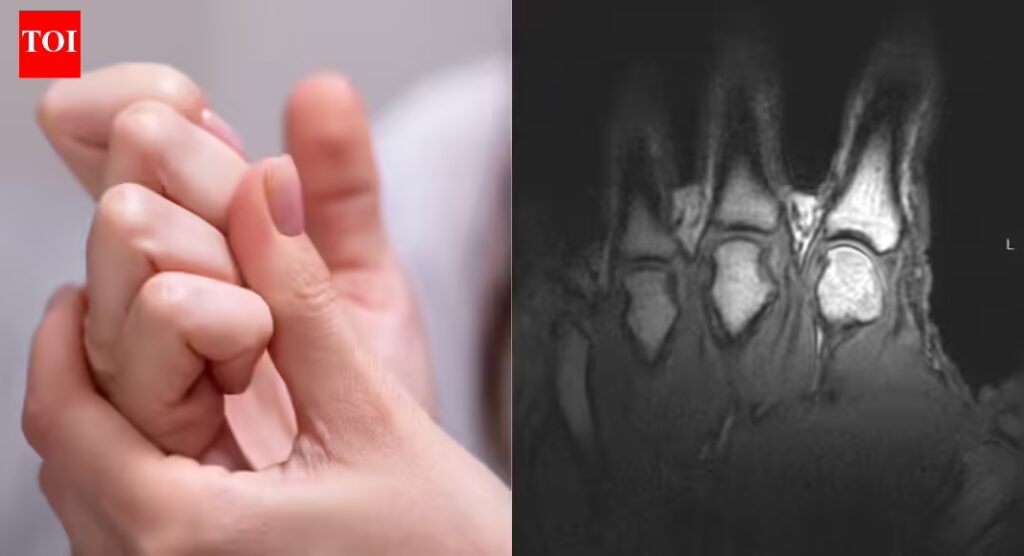

Researchers now agree that the sound produced when knuckles, toes or other joints crack is caused by gas, not bones grinding or cartilage snapping. A widely cited2015 studyused real-time MRI imaging to observe joints as they cracked, capturing the process as it happened rather than relying on theory alone.

The scans showed that when a joint is pulled or stretched, the pressure inside the joint space drops suddenly. Synovial fluid, the slippery liquid that lubricates joints, cannot fill the increasing space quickly enough. As a result, a gas-filled cavity forms inside the fluid. This process is known as tribonucleation, and the rapid formation of that cavity is what produces the distinctive popping sound.

Side by side MRIs revealing a gas bubble forming as joints in the fingers are cracked (University of Alberta)

Greg Kawchuk, a professor in the Faculty of Rehabilitation Medicine at the University of Alberta, described the process in simple terms while speaking to Science Alert.“When you do that, you can actually see very clearly what is happening inside the joints,” he said.“It’s a little bit like forming a vacuum. As the joint surfaces suddenly separate, there is no more fluid available to fill the increasing joint volume, so a cavity is created and that event is what’s associated with the sound.”This finding overturned earlier theories from the 1970s that suggested the noise came from gas bubbles collapsing rather than forming.